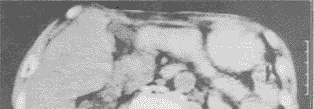

本组8例共作了12次CDU引导下TAE治疗术。其中,4例接受2次治疗,两次治疗的间隔时间为3~6周。术中从超声监视器上可见注入的化疗药物和栓塞剂呈微细点状回声,随血液流向肿瘤内部及其所在肝段/肝叶,并且引起病变范围组织回声水平的进一步增强。对非治疗区域行超声检查,未发现肝脏回声水平的显著变化。全部病例术后1~3天的CT扫描分析,证实栓塞剂准确进入肿瘤病变区域(图4,5)。接受本法治疗除了部分病例发生化疗后常见的胃肠道反应和白细胞下降等外,未发现治疗所致全身情况、肝肾功能等进一步明显恶化的证据。所有病例均未发生穿刺后的气胸、内出血、胆汁漏等严重并发症。

图4 术前CT扫描显示碘油未充填左肝肿瘤(箭头所示)

图5 术后CT扫描显示碘油完全充填左肝肿瘤(箭头所示)